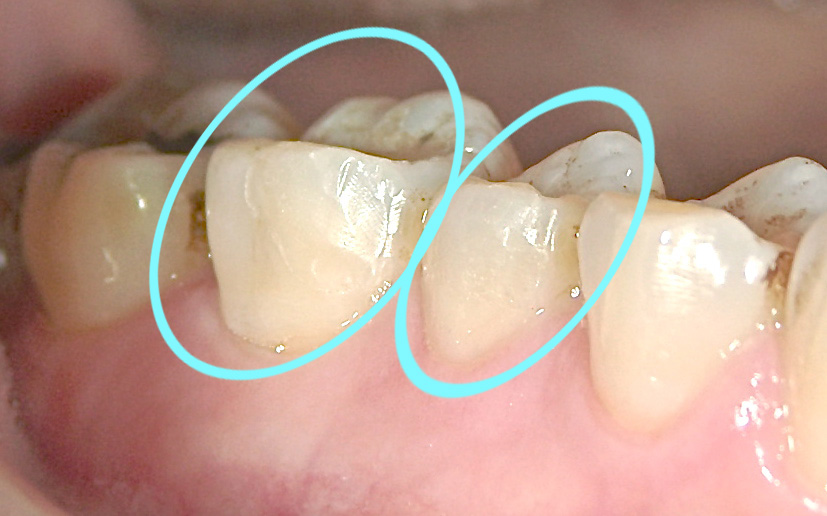

修復完了

コラム「修復完了」の画像